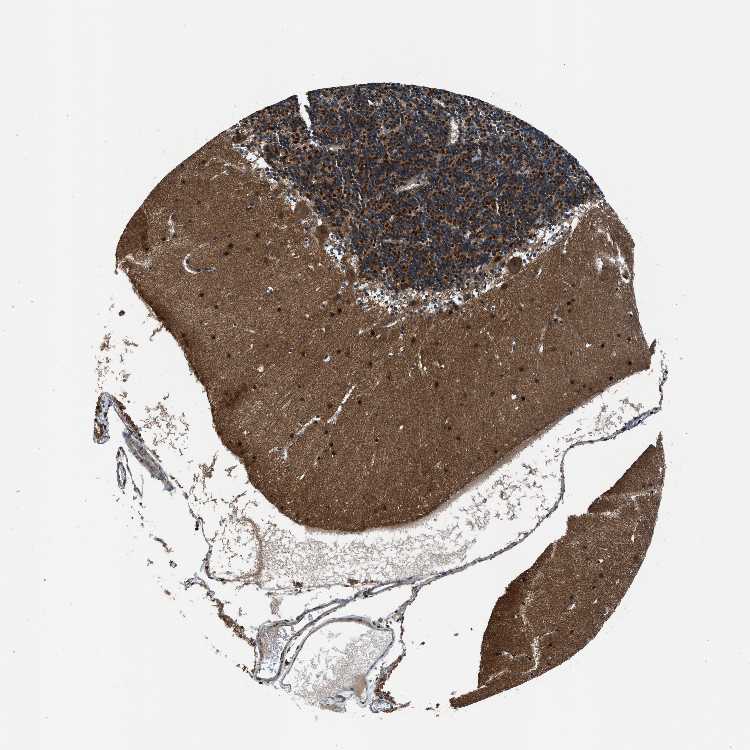

BRAIN CEREBELLUM Show tissue menu

CEREBELLUM - Expression summary

CEREBELLUM - Antibody stainingi

Antibody staining in the annotated cell types in the current human tissue is reported as not detected, low, medium, or high, based on conventional immunohistochemistry profiling in selected tissues. This score is based on the combination of the staining intensity and fraction of stained cells.

Each image is clickable and will lead to virtual microscopy that enables deeper exploration of all samples and also displays staining intensity scores, fraction scores and subcellular localization as well as patient and tissue information for each sample.

Antibody HPA011026Antibody HPA012037Antibody HPA014658

Purkinje cells LowMediumHigh

Cells in granular layer HighMediumHigh

Cells in molecular layer Not detectedLowHigh